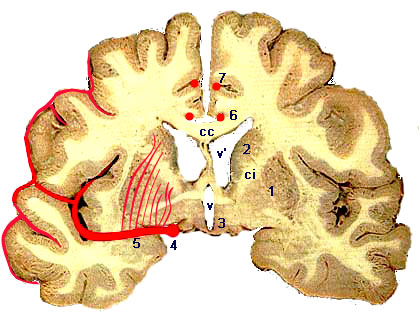

* Le primtre du polygone ainsi constitu partir de la carotide interne (1) et le tronc

basilaire (2) est dtermin :

-       en avant par les deux crbrales antrieures (6) et leur communicante (7),

-       latralement par les deux communicantes postrieures (4), et

-       en arrire par les deux crbrales postrieures (3) divergeant du sommet du tronc

basilaire.

* Le cadre artriel ainsi constitu est interpos entre le pourtour de la selle turcique et la base du diencphale circonscrite par le losange opto-pdonculaire.

De ce cadre se dtachent de nombreuses branches quon peut rpartir en deux groupes :

-       les artres centrales, courtes, elles perforent la face infrieure du cerveau pour atteindre les structures profondes ;

-       les artres corticales, longues cheminent en surface dans les sillons hmisphriques ; ce sont les artres crbrales antrieures, moyennes et postrieures.

-a et b: perforantes antrieures

-c et d: perforantes intermdiaires

-e: groupe postrieur

cc: corps calleux

-ci: capsule interne

-v: 3 ventricule

-v': ventricule latral

-1: noyau lenticulaire

-2: noyau caud

-3: noyaux hypothalamiques

-4: artre crbrale moyenne

-5: artres stries

-6: artre pricalleuse

-7: artre calloso-marginale

Coupe frontale du cerveau (Charcot)